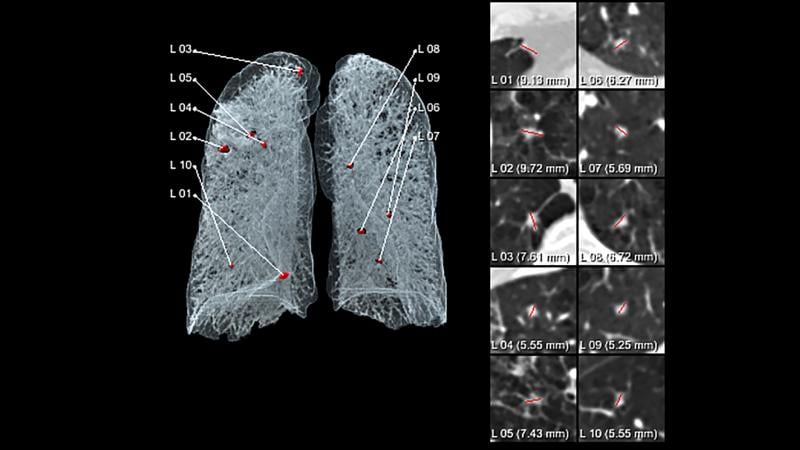

Another aspect of AI is diagnostic support. AI algorithms can work in the background to automatically identify regions of interest on images, including FDA-cleared applications to identify pneumothorax, improper placement of endotracheal tubes, if a patient has a stroke and whether it is ischemic or hemorrhagic, the presence of tumors, or to red flag incidental findings that are outside the main area of the exam’s protocol.

AI is also being baked into systems to automatically identify anatomy, key image views for reads, set-up of specific radiologists’ hanging protocols, and to automatically make key measurements. AI is also being used to autofill sections of radiology reports with measurements or common paragraphs of text based on findings of what the AI sees or measures in the images. All of these measures help speed workflow and often act as a second set of eyes for the radiologist. The radiologist still maintains control in being able to override and edit anything the artificial intelligence has added.